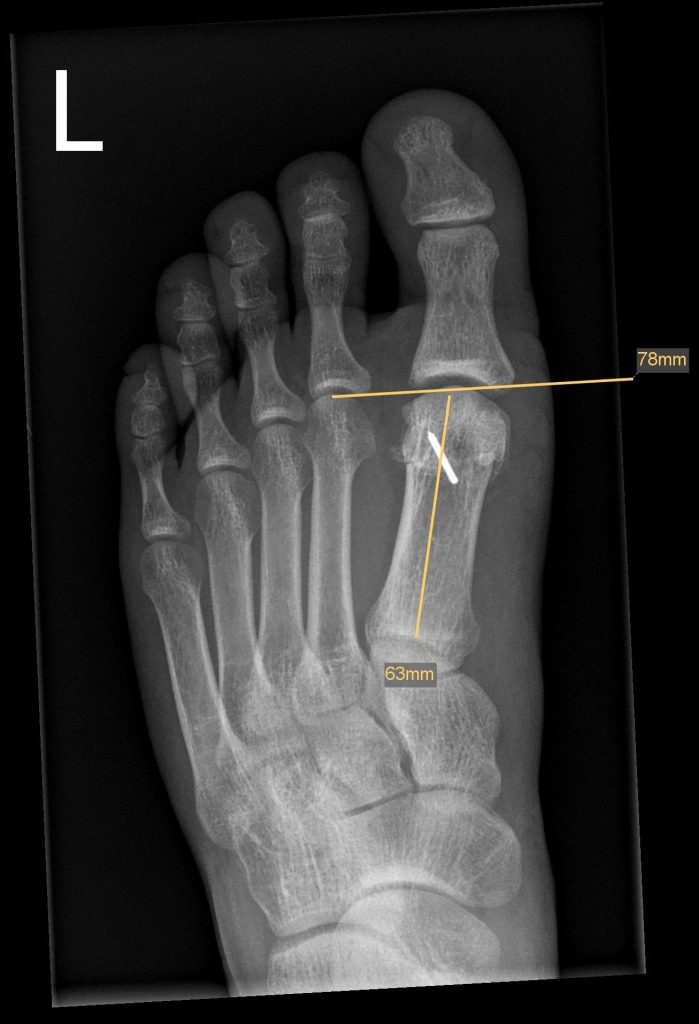

- Röntgen zur Beurteilung von Gelenkspalt, Osteophyten, Stellung

Youngswick Osteotomie

(Arthrose Gelenkspalt mehr als 50%, langer erster Mittelfußknochen)

Ist eine Modifikation der Chevron-Osteotomie ( OP bei Hallux valgus) dabei wird eine V- Förmige gelenknahe Durchtrennung des ersten Mittelfußknochens durchgeführt . ( in Kombination mit einer Cheilotomie) und eine Knochenscheibe entnommen, dadurch kommt es zu einer Verkürzung des ersten Strahls und einer Druckentlastung des Gelenks, was einer Verbesseerung der Beweglichkeit und Reduzierung der Schmerzen führt. Diese Operation führen wir häufig bei noch erhalten Gelenkspalt als Alternative zur Versteifung durch.